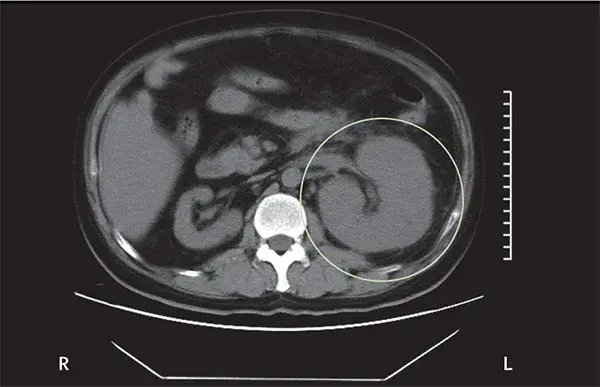

Os cálculos coraliformes são formados em sua maioria por cálculos de estruvita (fosfato amônio de magnésio) e possuem uma forte associação com infecção do trato urinário (ITU) causada por bactérias produtoras de urease. A formação desses cálculos é rápida, semanas a meses, e se não instituído tratamento adequado pode ocorrer invasão completa do sistema coletor